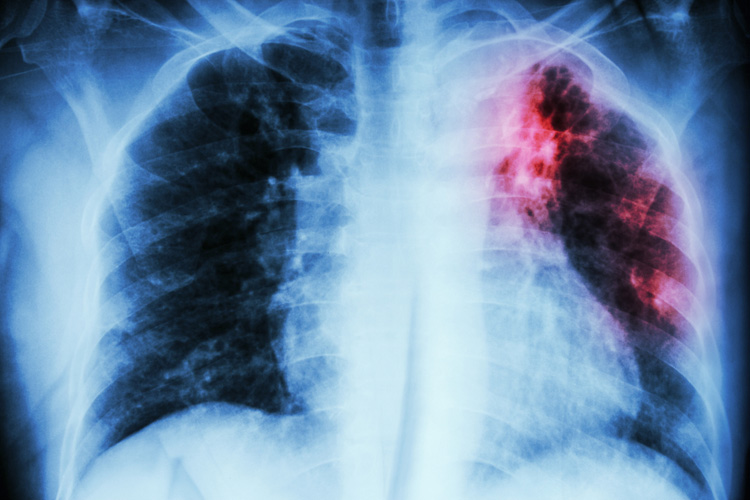

В Узбекистане обсуждают расширение применения науки и технологий в решении проблемы туберкулеза